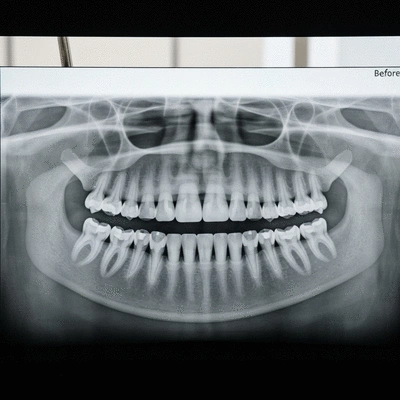

Avant de commencer tout traitement, une évaluation approfondie de votre dentition est essentielle. Cela inclut généralement un examen clinique et des radiographies dentaires pour analyser la position de vos dents et de votre mâchoire.

Les résultats parlent d'eux-mêmes ! Dans notre cabinet à Rouen, j'ai eu le plaisir de voir de nombreux patients adultes transformer leur sourire. Voici quelques exemples inspirants :

Je partage souvent des cas avant/après avec mes patients pour leur montrer ce qui est possible. Ces transformations démontrent non seulement l’efficacité des traitements, mais aussi l'impact positif sur la vie quotidienne des patients.